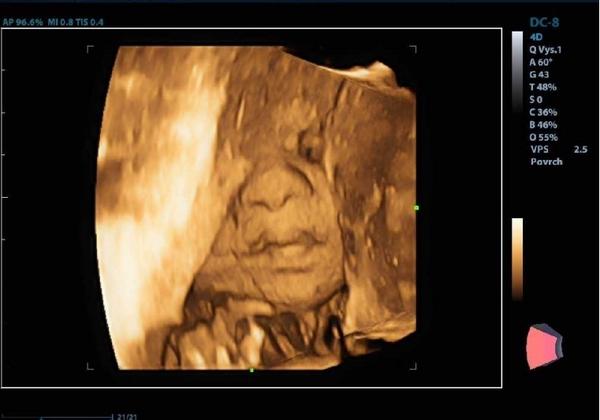

@tercasv ony ty cizí fotky na internetu jsou něco jiného, než když pak člověk vidí toho svého cvrčka 🙂 Mě tedy zase tak moc neoslovily přímo ty fotky - byť se nám povedly docela hezky, ale líbil se mi ten zážitek. Je vidět, jak se tam miminko tváří, jak zívá, dělá ksichtíky........🙂

Za mě fajn cesta do hlubin ...maminčina bříška - moc me bavilo, když jsem pak našla fotku ze 3D a fotku reálnou, které byly témeř totožné - tvář, výraz......

@tercasv Ja od toho moc neocekavala, premluvil me manzel, ze to zkusime, ze bychom treba litovali. Malej se nechtel ukazat oblicejem, takze jsme si dobre prohledli jeho zadek a naprosto presne vedeli, ze to bude kluk🙈 Pak se ale ukazal a stalo to za to. Mam fotku, kterou mam stale vytavenou na stole a rada se koukam, jak si byl po narozeni podobny, vcetne jeho mimiky😀 U me to tedy predcilo ocekavani, nejen ten vysledek, ale i ten zazitek byl fajn😀.

Stojí - ale až tak v tom cca 23-28 týdnu 🙂 to už je krásně vidět obličejík. Já mám od dcery i syna i moc pěkná videa 🙂